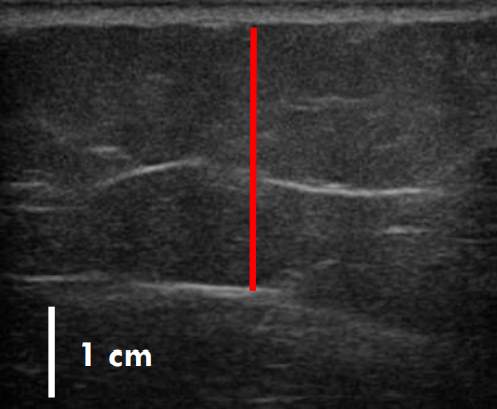

트루스컬프 아이디 시술 전, 12주 후 초음파를 비교한 사진입니다.

레드 라인이 지방층의 두께입니다.

앞서 보여드린 사례의 경우 시술 전과 비교했을 때 약 36% 정도 지방이 감소한 결과를 볼 수 있는데요.

이 정도의 지방량을 줄이려면 일반적인 운동, 식이요법만으로는 한계가 있지요.